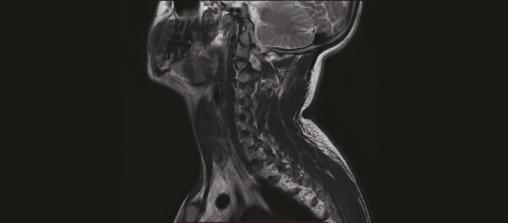

Un homme de 21 ans est admis en service de réanimation pour convulsion fébrile, quelques semaines après avoir été rapatrié d’une mission en zone d’endémie palustre pour des crises convulsives. Le diagnostic d’un accès palustre à Plasmodium falciparum est confirmé. L’évolution est marquée par la survenue d’un déficit moteur et sensitif au niveau des deux membres supérieurs avec une amyotrophie des muscles de la ceinture scapulaire ; un syndrome de Parsonage-Turner post-infectieux est suspecté (fig. 1 ). Un électromyogramme, une imagerie par résonance magnétique (IRM) du plexus brachial (fig. 2 ) et un scanner des épaules sont en faveur d’une luxation antérieure post-convulsive des deux épaules (fig. 3 et 4 ).